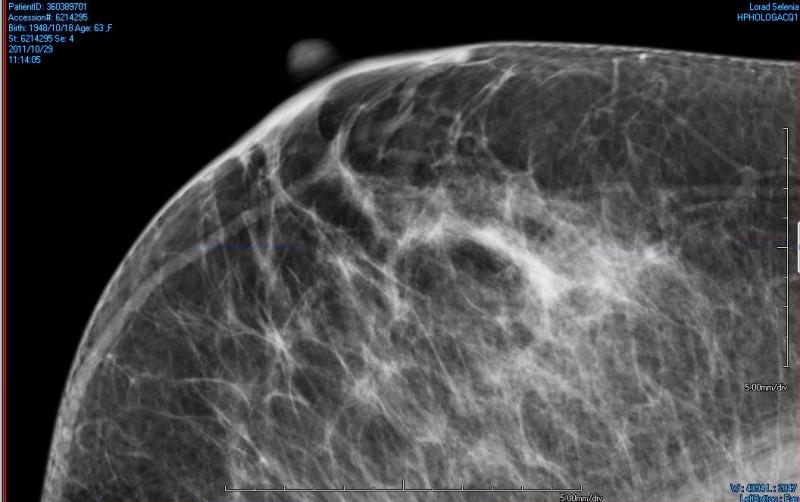

In an era of increasingly personalized medicine, patients are expecting more tailored approaches to care from their physicians. Mammography, long the gold standard for routine breast cancer screening, is no longer enough for a majority of women who find themselves at higher risk for breast cancer due to breast density. The issue of density, which limits the benefits of mammography, has been making its way to the forefront of breast cancer discussion in recent years, and advocates are pressing many in the healthcare community to reconsider their routine annual screening programs in order to save more lives.

Patients are noticing the difference since Rye Radiology implemented 3D mammography more than two years ago, in 2012. Some are amazed they no longer need extra views. Some are grateful their 3D exam found that suspicious lesion when it was small and easier to manage. At least one patient credits the 3D exam with saving her life.

Hologic, Inc. announced that the Centers for Medicare and Medicaid Services (CMS) has released reimbursement rates for screening and diagnostic 3-D mammography. The action establishes national average payment rates for the Category I Current Procedural Terminology (CPT) code for 3-D screening mammography and creates a new add-on Healthcare Common Procedure Coding System (HCPCS) code for 3-D diagnostic mammography.

Fujifilm Medical Systems will highlight its women’s healthcare portfolio at the 2014 Radiological Society of North America (RSNA) in Chicago, Ill. The company will show enhancements to its Aspire Cristalle mammography system, released in July.